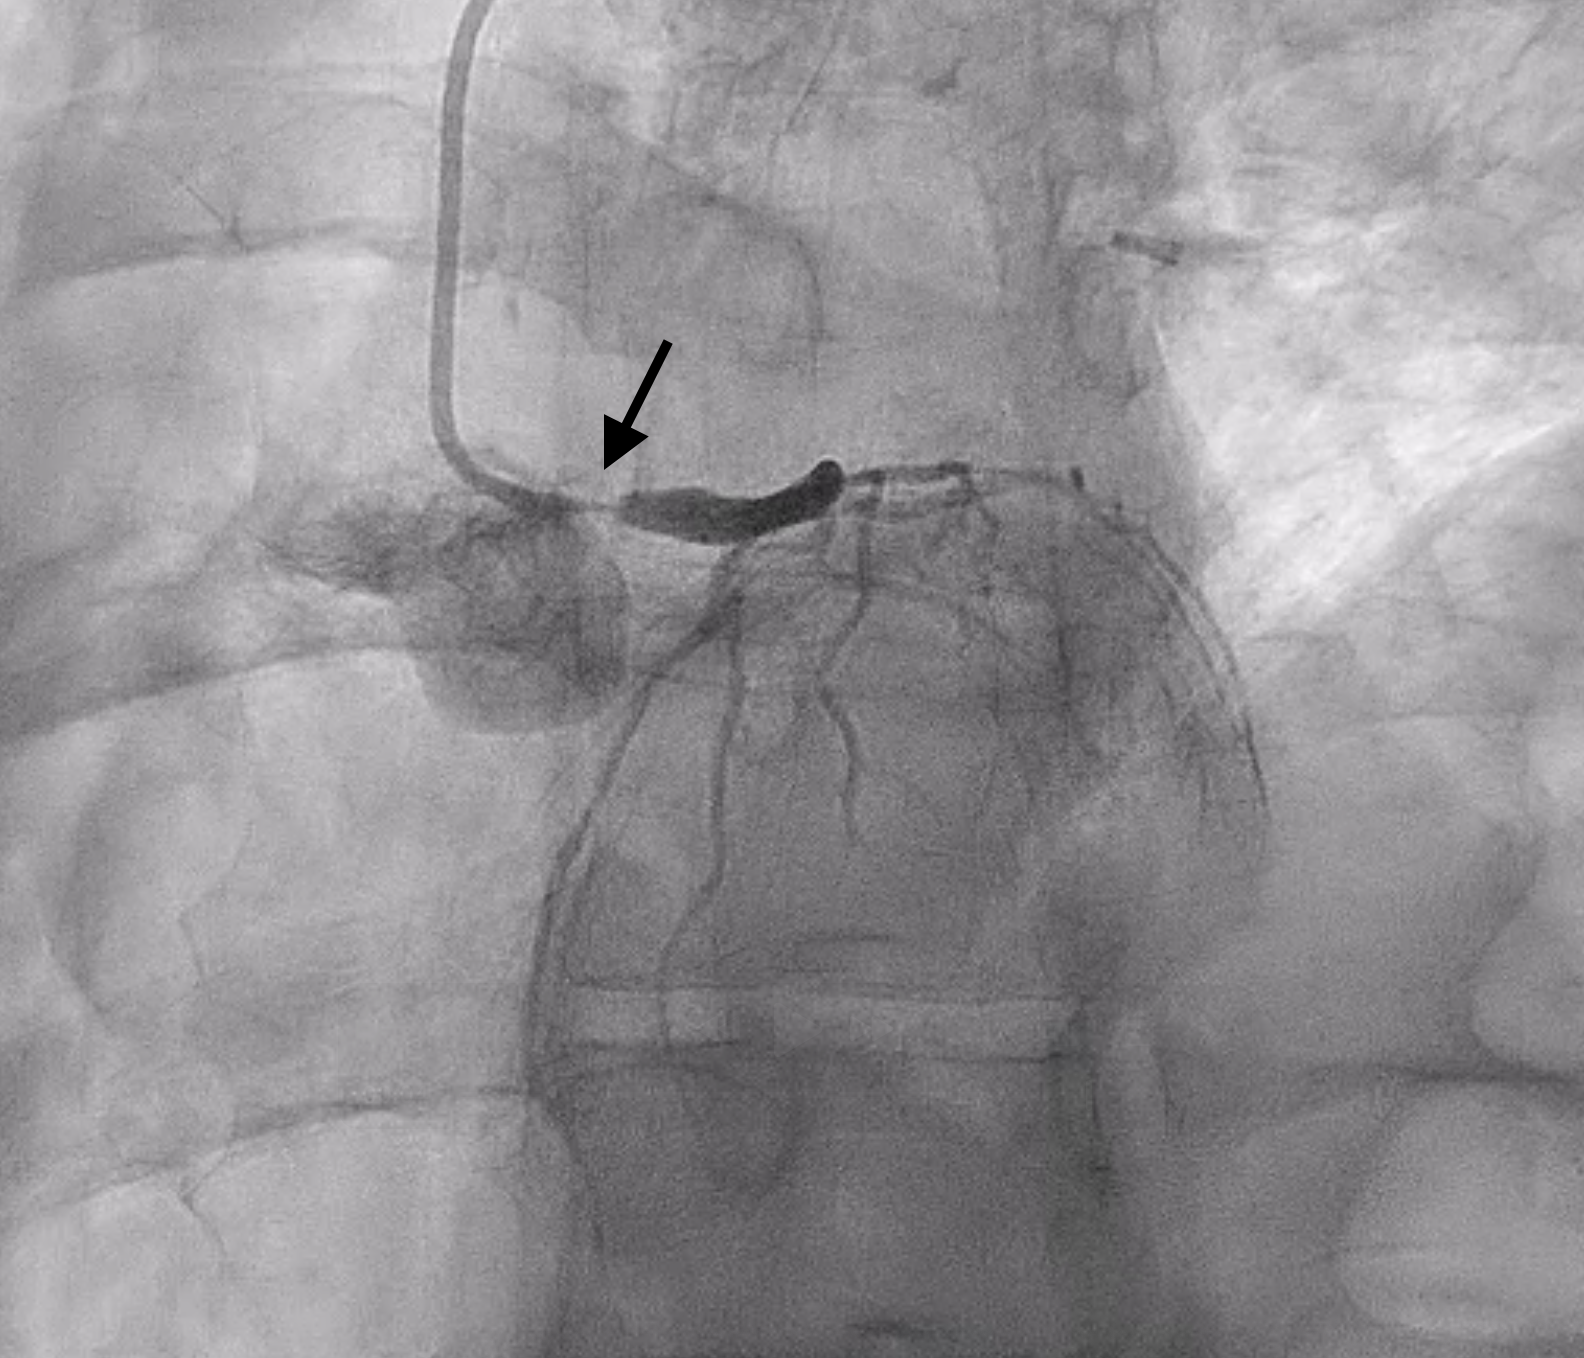

Left main has ostial to mid lesion with 90-95% stenosis. Left anterior descending and left circumflex and right coronary arteries have luminal irregularities without angiographic evidence of obstructive disease. Extreme angles were avoided during diagnostic angiogram in setting of her active pregnancy.

Patient had significant spasm of the bilateral radial arteries so right femoral artery access was obtained. A 6 Fr EBU 3.0 guide catheter was used to engage the left main coronary artery. A Sion wire was advanced into the LAD and a Sion Blue wire was advanced into the left circumflex. Pre-dilation was performed with a 2.5 x 12 mm semi-compliant balloon. IVUS showed MLA of 1.5 mm2 with intramural hematoma and evidence of plaque and thrombus. There was no evidence of SCAD on IVUS imaging. A 4 x 18 mm DES was placed in the left main and post-dilated with a 4.5 x 15 mm and 5 x 8 mm NC balloon. Final angiogram and IVUS confirmed excellent stent expansion/apposition with large MSA (11.8 mm2) and proximal stent edge in the ostium of the left main. Total air kerma was <500 mGy and and DAP was 50 Gy-cm2.